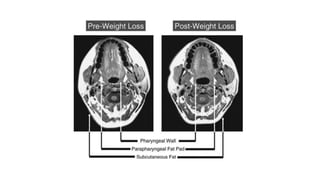

MRI/VOLUMETRIC MRI

Best current mode of imaging for assessment of the upper airway and

surrounding soft tissue and craniofacial structures

MRI studies helped us in under standing

• Pathophysiology of sleep(OSA)

• Mechanisms undelynig treatments like

• Weight loss

• CPAP

• Oral appliances

• Upper airway surgery